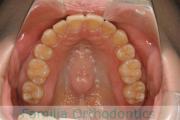

No.22V-449

- 主な症状:

- 上顎前突

- その他の症状:

- 叢生

- 年齢:

- 14歳

- 性別:

- 男性

- 抜歯部位

- 上:

- 44

- 下:

- 8448

- 主な使用装置:

- FEA

- 治療にかかった費用:

- 87万円

歯並びをきれいにしたいということで来院されました。上下左右から小臼歯を抜歯して、マルチブラケット法を行っています。2年弱、25回程度の通院が必要でした。

かなり強い叢生(でこぼこ、凹凸、ガタガタ)ですので、保定をしっかりしないと後戻りのリスクがあります。

- ≫治療後

-